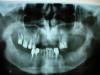

корвин Опубликовано 7 апреля, 2009 Поделиться Опубликовано 7 апреля, 2009 Сломался верхний передний мост. Один врач попытался восстановить его только на вкладках клыка. Выскочил через 10 дней. В результате пришлось удалить даже корень третьего зуба. Пока месяц возились один за другим сломались два нижних моста - разрушились зубы под коронками. Месяц без зубов. Ни поесть ни улыбнуться. Работа - с людьми. С другим врачом планировали установить два съемных протеза (верх и низ). Вверху планировали бюгельный или из денталура. Внизу пластинчатый или так же - денталур. Но долго не заживает ранка, а без этого не установить протез вверху. Вопрос: я решил временно установить вверху несъемный литой мост на имеющиеся зубы (на сохранившемся корне будет вкладка). Если мост прослужит хотя бы год - я буду удовлетворен. Гарантии - не потребую. Заживет ранка, наконец то смогу поесть и разговаривать с людьми. А уже потом, когда все же мост выйдет из строя, буду ставить съемный протез. Врач - в сомнении. Я тоже. Так же буду рад услышать советы о выборе материала и вида протезов и даже о возможности имплантации в будущем, хотя видимо мне это будет не по карману. А вот нейлоновый протез смог бы оплатить. Действительно ли он настолько удобнее как рекламируют?Спасибо за ответы. Ссылка на комментарий

корвин Опубликовано 7 апреля, 2009 Автор Поделиться Опубликовано 7 апреля, 2009 если где-то что-то не заживает, значит есть какая-то проблема. Ее надо решать. Зуб удален неделю назад. Это нормальные сроки.Не понятно мне желание "временно" ставить литой мост.Наружная стенка десны - "ушла" вообще Заживать будет еще несколько недель. Так что любые съемные протезы - не установить! Очень трудно терпеть столько без нормальной еды. Контакт есть только у одного зуба. И внешний вид огорчает.У Вас есть зубы, нуждающиеся в перелечивании, есть, нуждающиеся в удалении...Все зубы на снимке - уже вылечены. Требующие удаления - удалены. Штифты и вкладки - вставлены. На корне тройки - уже тоже вкладка.Нейлоновые протезы показаны при малых и средних дефектах.Спасибо! Весьма убедительно. Значит нейлоновые отпадают. Вопрос:Каково Ваше мнение - литой мост сможет продержаться год? Думаю, что не забуду об аккуратности при еде.Денталур - нечто среднее между пластмассой и нейлоном. Мне он представляется более симпатичным по цене и характеристикам. Для постоянного съемного протеза, пока только для нижней челюсти.А Вам? Ссылка на комментарий